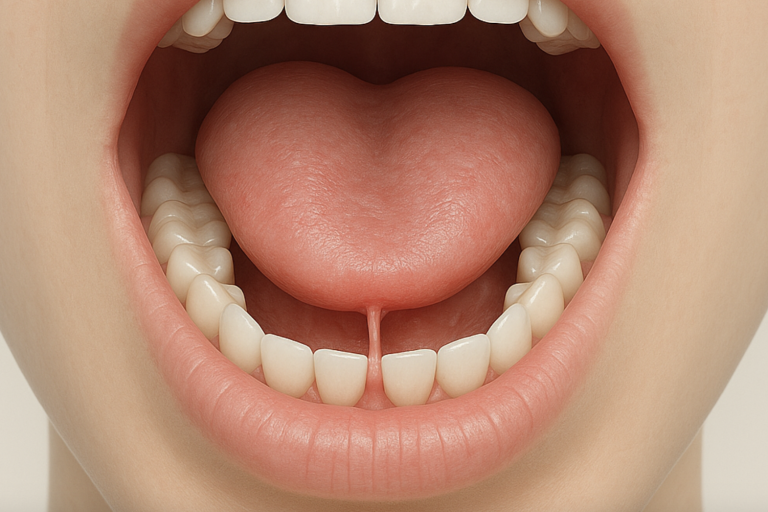

Frein lingual

Freins buccaux

La chirurgie est asssitée d'un laser